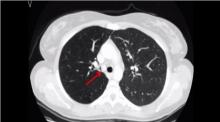

This video demonstrates the technical details of an endoscopic radical resection of an endobronchial carcinoid by laser-assisted rigid bronchoscopy. A 35-year-old woman with a history of cough and asthma was referred for acute hemopysis. A chest CT scan disclosed a round, well-defined mass occluding the right main bronchus; no lymph nodal involvement or tracheo-bronchial wall infiltration was evident. Flexible bronchoscopy confirmed that the right main bronchus was fully occluded by a mobile lesion. Biopsy disclosed a typical carcinoid with a proliferation fraction of 2% and a proliferation index of 1 mitosis/10 high powered fields (HPF).